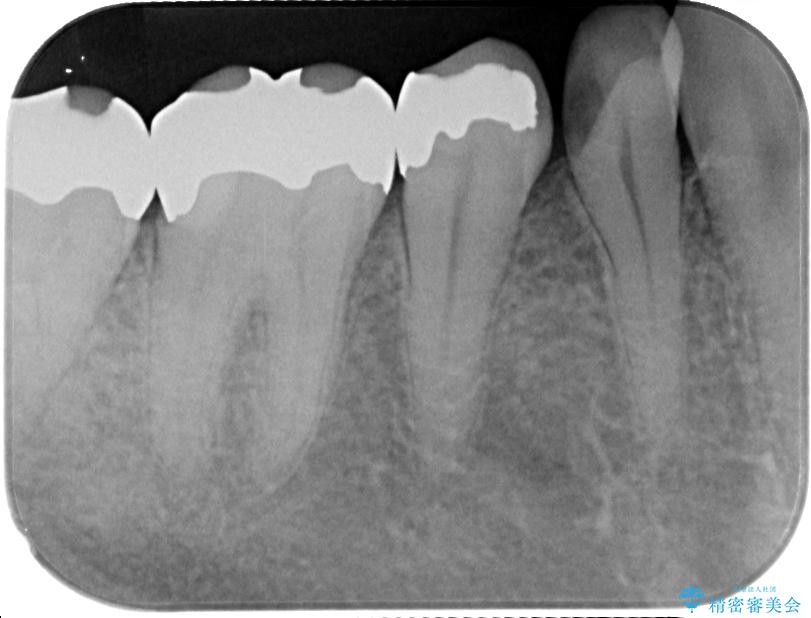

- 右下の銀歯が取れたとのことで来院された患者様です。以前にも取れていたところで、メタルインレーの不適合も認めていたため、次回外れたらオールセラミッククラウンにやり替えていくことを説明していたため、オールセラミッククラウンによる補綴治療を行っていくことにしました。

拡大鏡視野下で虫歯を除去しオールセラミッククラウンに適した形に整えました。

歯と歯茎の間に圧排糸と言われる糸を入れてシリコーン印象材にて型どりをしました。